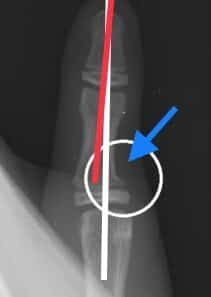

さわやか千葉県民プラザ(指骨骨折)